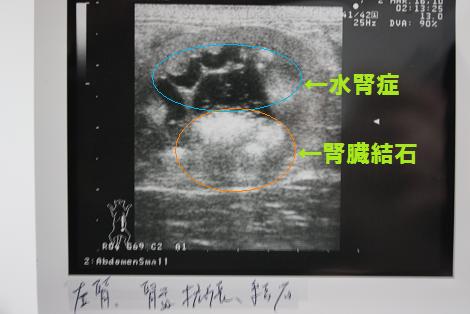

エコーでみると左側の腎臓が水腎症を起こしていて、腎臓内にも

結石が・・・。右側の腎臓にも少し水腎症が見られる。結石もある

という事だったのでここでも点滴だけしてもらい帰りました。